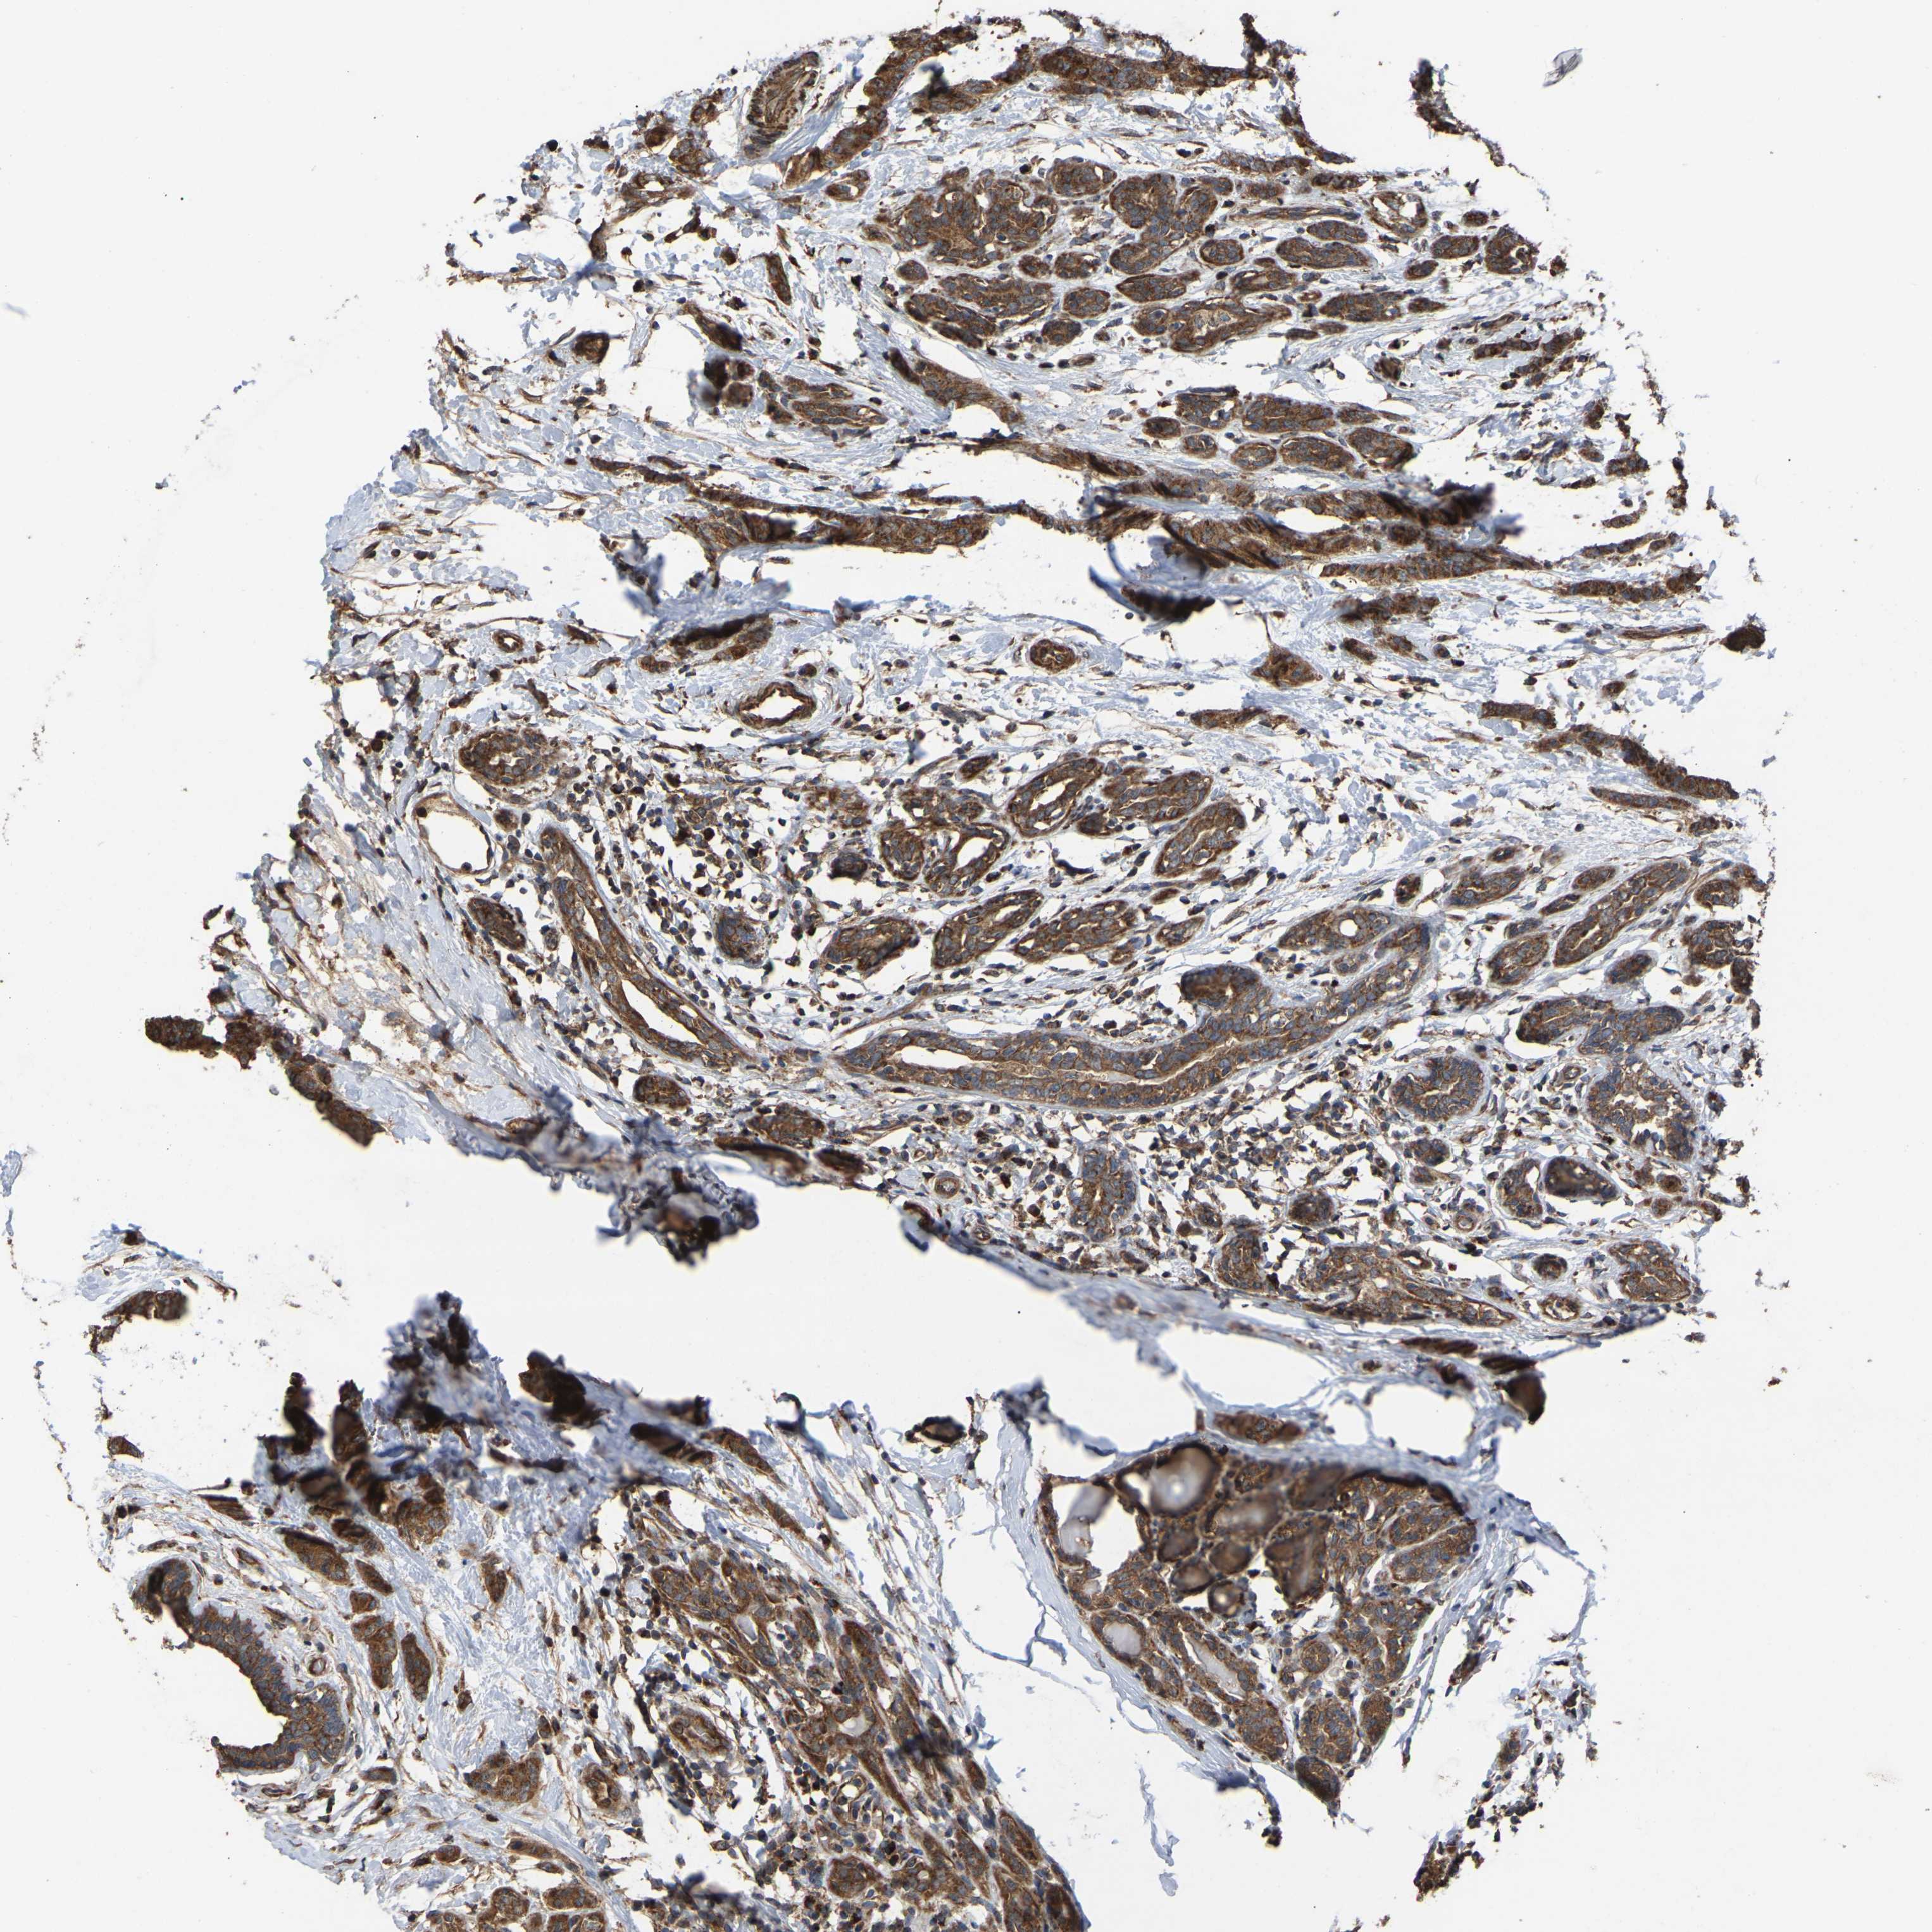

CANCER BREAST CANCER Show tissue menu

BRCA TCGA BRCA VALIDATION PROTEIN EXPRESSION